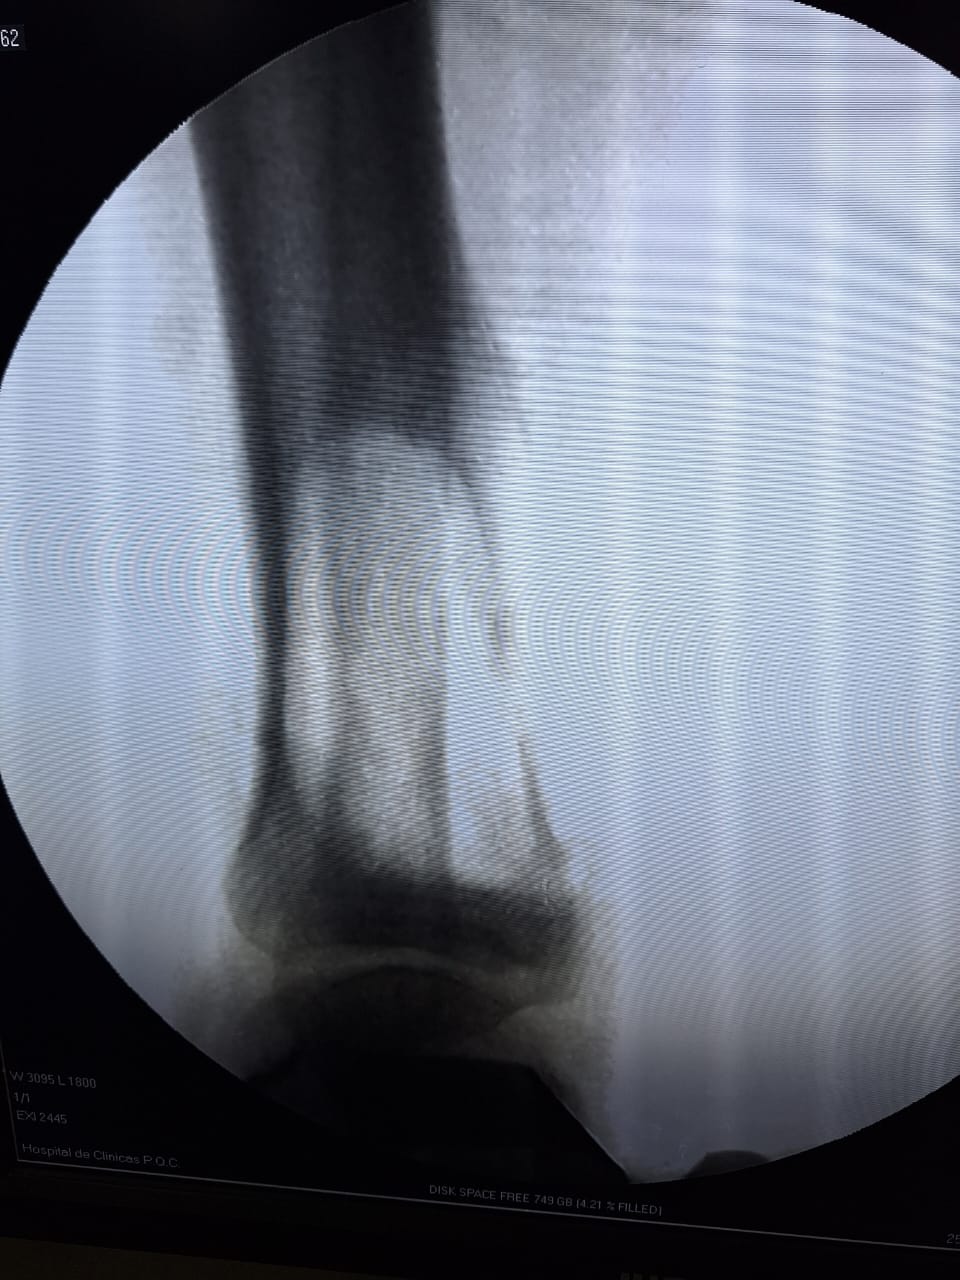

El Prof. Dr. Hernán Servín, Especialista de la Cátedra y Servicio de Traumatología, explicó que la cirugía fue llevada a cabo a un paciente del sexo masculino de 17 años con una tumoración ósea en el tercio distal de la pierna derecha, específicamente en el hueso de la tibia, el mismo proviene de la ciudad de Encarnación. Este procedimiento corresponde a exéresis de proceso tumoral, fenolización relleno de defecto óseo tumoral con injerto de banco y estabilización con Osteosíntesis.

Cabe resaltar que el paciente ya se había tratado en su ciudad de manera inicial, donde fueron realizadas dos biopsias y una tercera fue hecha en el Hospital de Clínicas, arrojando resultados de una tumoración ósea benigna, el cual es un tumor de células gigantes.

“La operación tuvo una duración de tres horas, y se espera un periodo de reposo postoperatorio de aproximadamente 16 semanas para la consolidación del injerto”, acotó.